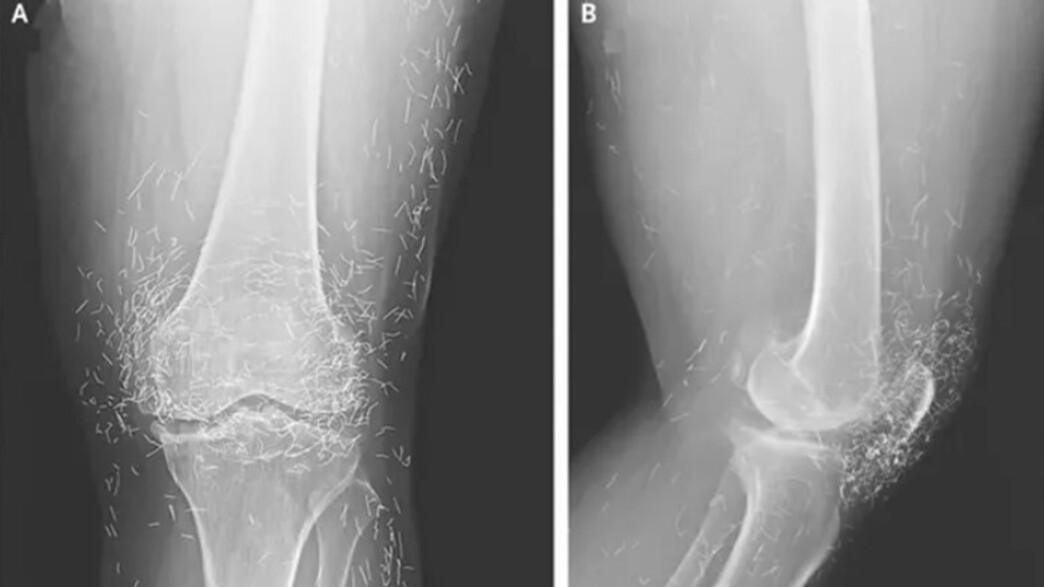

מאות חוטי זהב טהורים אותרו בגוף מטופלת בקוריאה הדרומית, שמה לא פורסם ברשתות, שסבלה בעבר מכאבים חמורים ומנוקשות בברכיים עקב דלקת מפרקים ניוונית (אוסטאוארתריטיס).

בדיקת רנטגן שעברה במקום חשפה ממצאים מטרידים: עיבוי והתקשות של החלק הפנימי של עצם השוקה, גידולים גרמיים בברך - ומאות חוטי זהב זעירים טמונים ברקמות שסביבה.